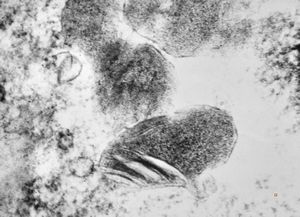

F,50y. | progressive multifocal leukoencephalopathy- viral particles in a glial cell

F,50y. | progressive multifocal leukoencephalopathy- viral particles in a glial cell

F,50y. | progressive multifocal leukoencephalopathy- viral particles in a glial cell